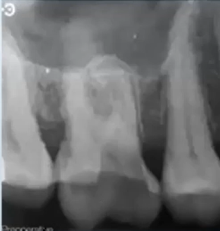

how to explain tx options to pt

list all tx options - split into immediate (pain relief), medium term, long term

explain risks and benefits of each option

explain it must be holistic decision taking into account the pt concerns, MH. OH, financial cost and biologic cost (price of the teeth/mouth will have to pay if go ceratin option)

IMMEDIATE MANAGEMENT

give cooling period for pt to have time to decide